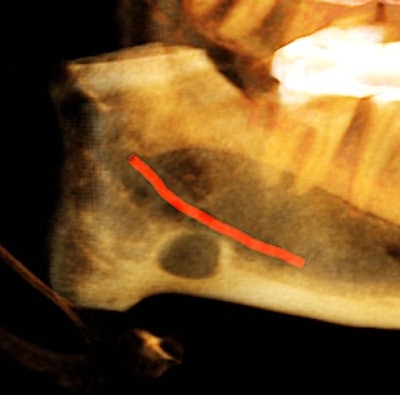

The oral surgeon ordered a cone-beam CT (CBCT) exam. Click images below to enlarge. In order: reformatted panoramic radiograph and cropped image of the area of interest, coronal view of the posterior right mandible (the inferior alveolar canal in red), and 3D reconstructed image of the posterior right mandible.

Figure 4: Coronal view of the posterior right mandible (the inferior alveolar canal highlighted in red) and 3D-reconstructed image of the posterior right mandible.

There is a hypodense lesion (radiolucent) that is well-defined, well-corticated, oval in shape, 8 x 6 mm, located at the posterior right mandible, and distal to tooth #32. The lesion is located below the inferior alveolar canal. No expansion is observed in the cross-sectional views. No calcifications are observed inside the lesion.

From the radiographic perspective, Stafne bone defects are radiolucent lesions, well-defined and well-corticated, oval in shape, and located below the inferior alveolar canal. No expansion is usually observed in the coronal views.

The differential diagnosis includes benign and malignant lesions; however, the location below the inferior alveolar canal is an anatomical landmark that helps to differentiate a Stafne bone defect from odontogenic lesions (usually located above the inferior alveolar canal).